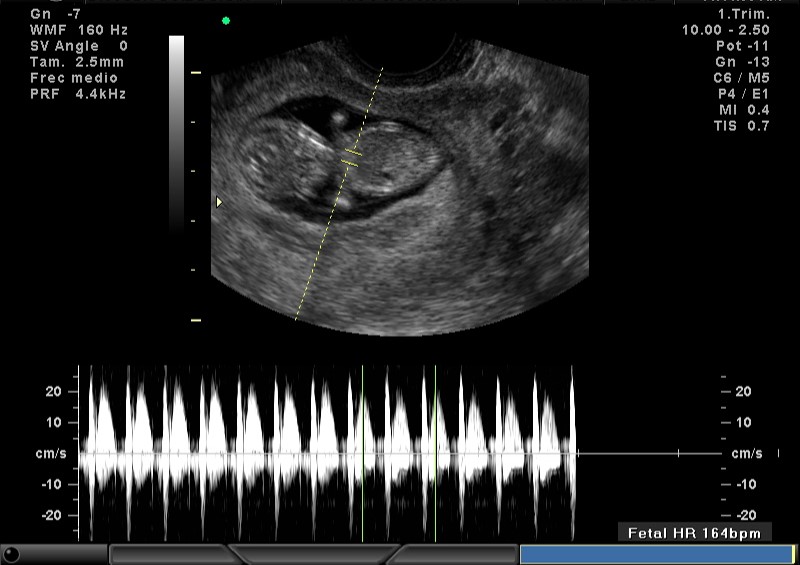

2D FRECUENCIA CARDIACA 9.5 SEMANAS

2D FRECUENCIA CARDIACA 10.5 SEMANAS